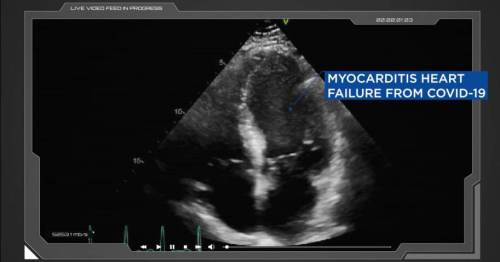

“A frightening new potential explanation for vaccine-driven myocarditis and other problems

Researchers in the New England Journal of Medicine raise the possibility of an uncontrolled autoimmune response to the coronavirus spike protein that may last indefinitely

Downstream effects of the antibodies that people produce against the coronavirus spike protein may lead to myocarditis and even neurological concerns, two veteran medical researchers have written in the top medical journal in the United States.

To be clear, the researchers did not provide proof that these anti-idiotype antibodies are actually causing problems, or even that they exist. The paper merely presents a theory. But the writers believe it could explain the high incidence of myocarditis “after vaccine administration” and even “neurologic effects of SARS-COV-2 infection or vaccines.”